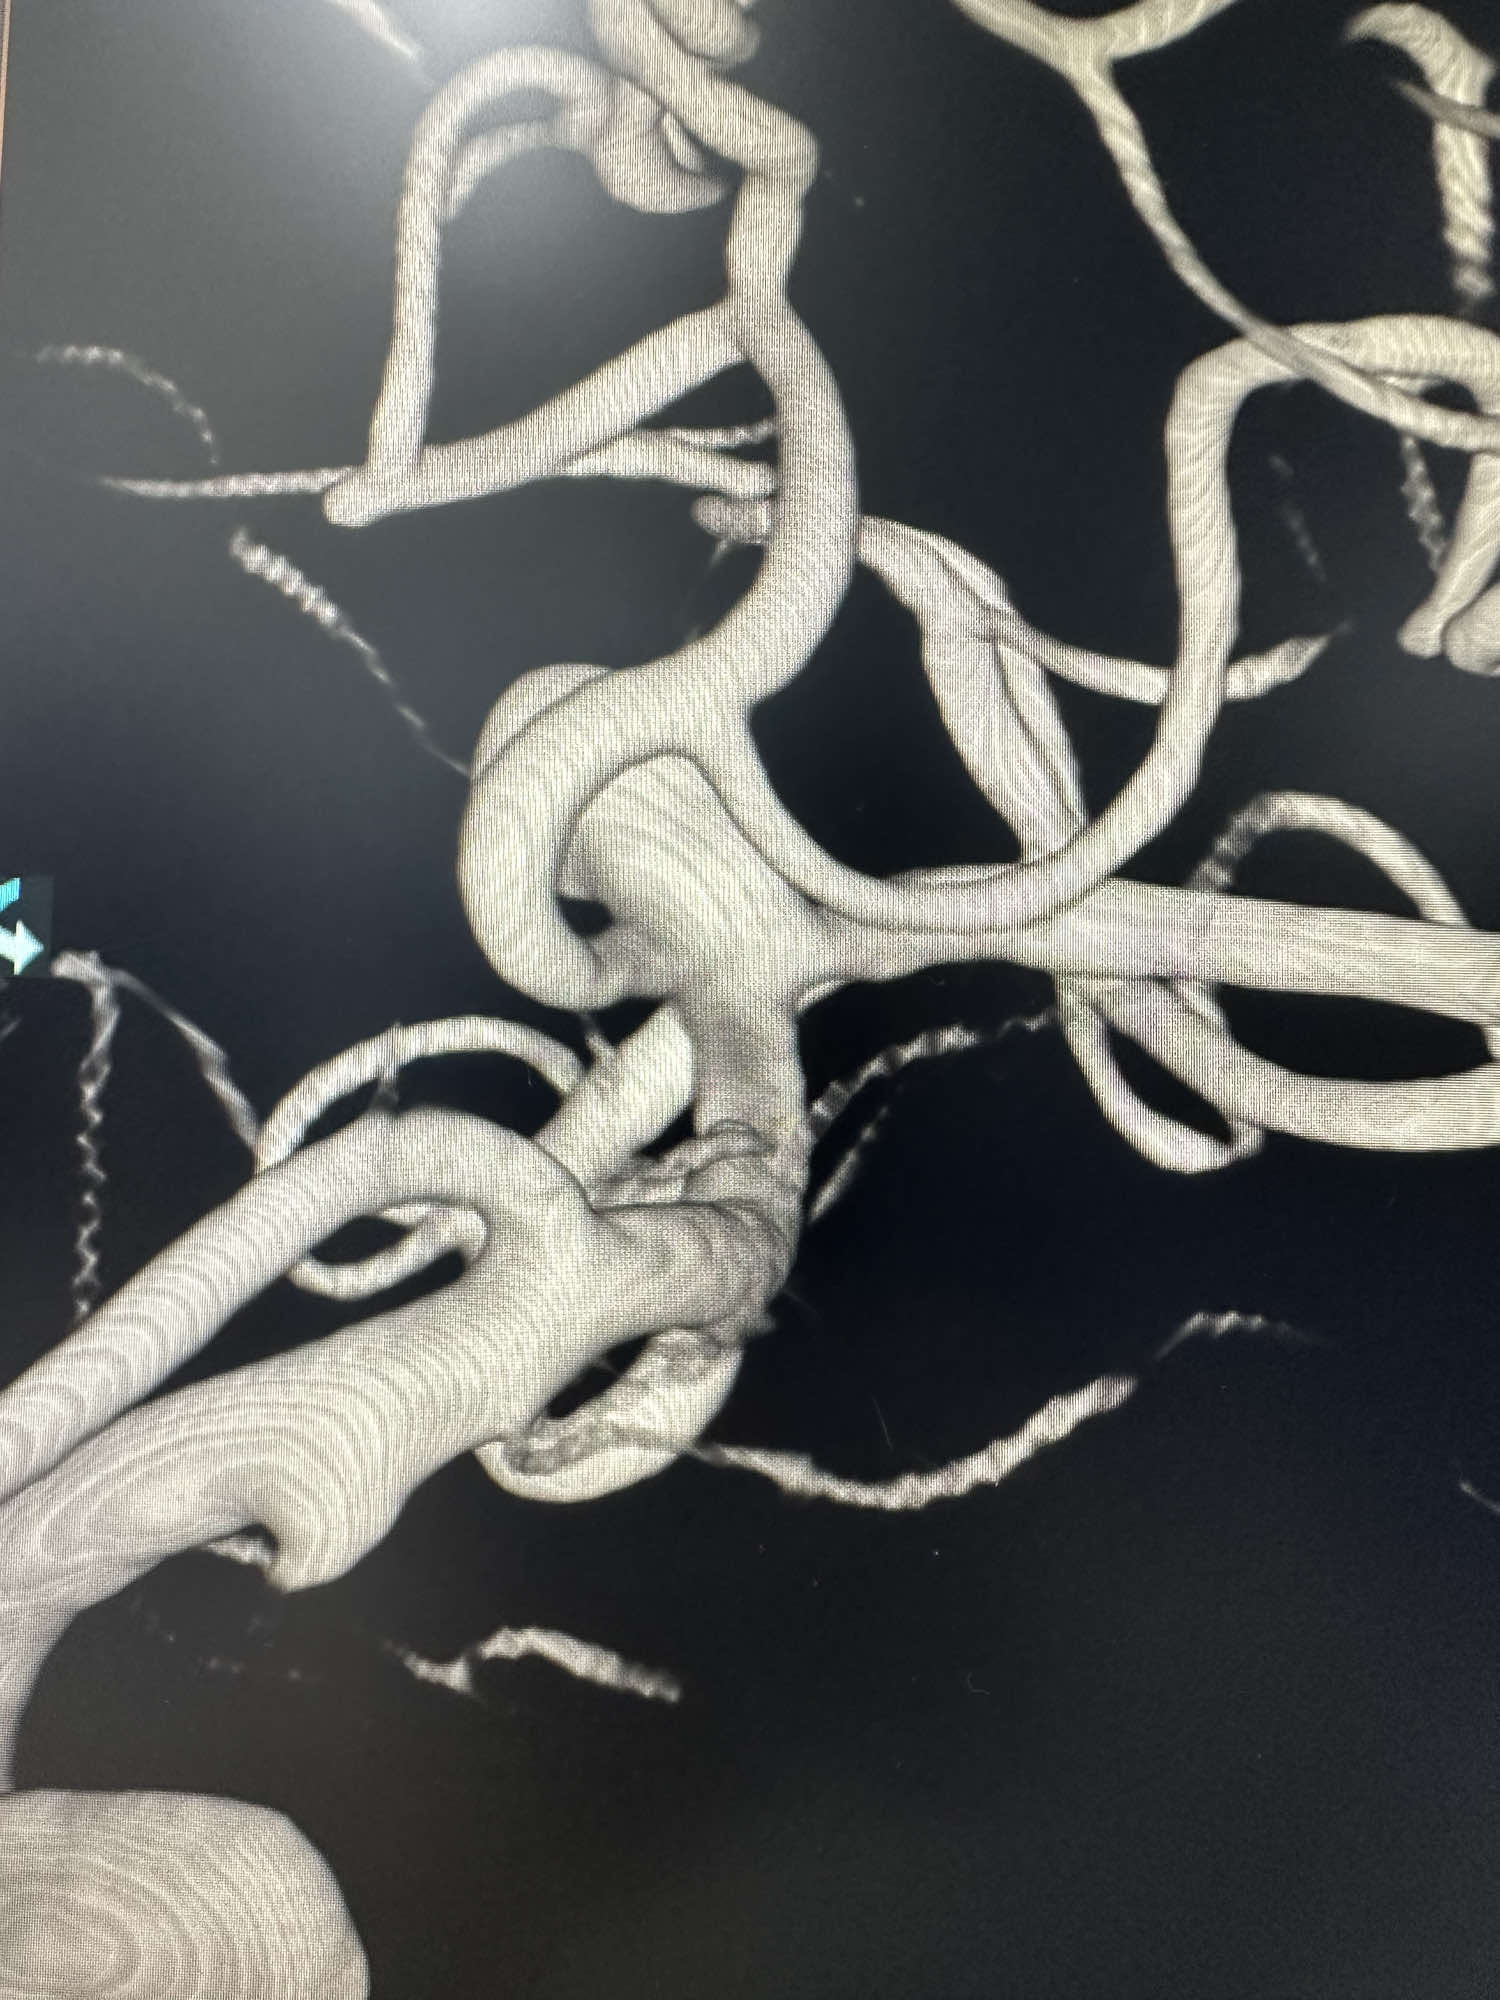

右侧颈内动脉3D发现右侧大脑中分叉处一宽颈动脉瘤.

大脑中分叉处的动脉瘤

同侧的大脑中颞下干有一个宽颈动脉瘤